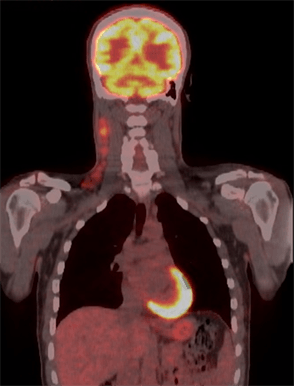

PET-CT Scans Performed 2022-2023

At our institution, lymphoma accounts for 19% of all PET-CT scans performed..